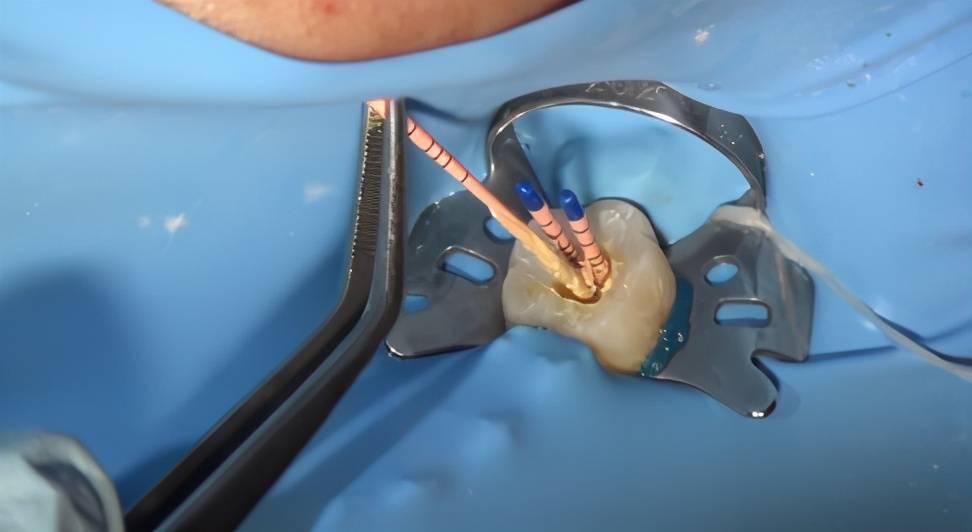

口腔技术 | 牙神经拔不净?关于根管治疗中拔净牙髓的技巧

图片尺寸1013x1663